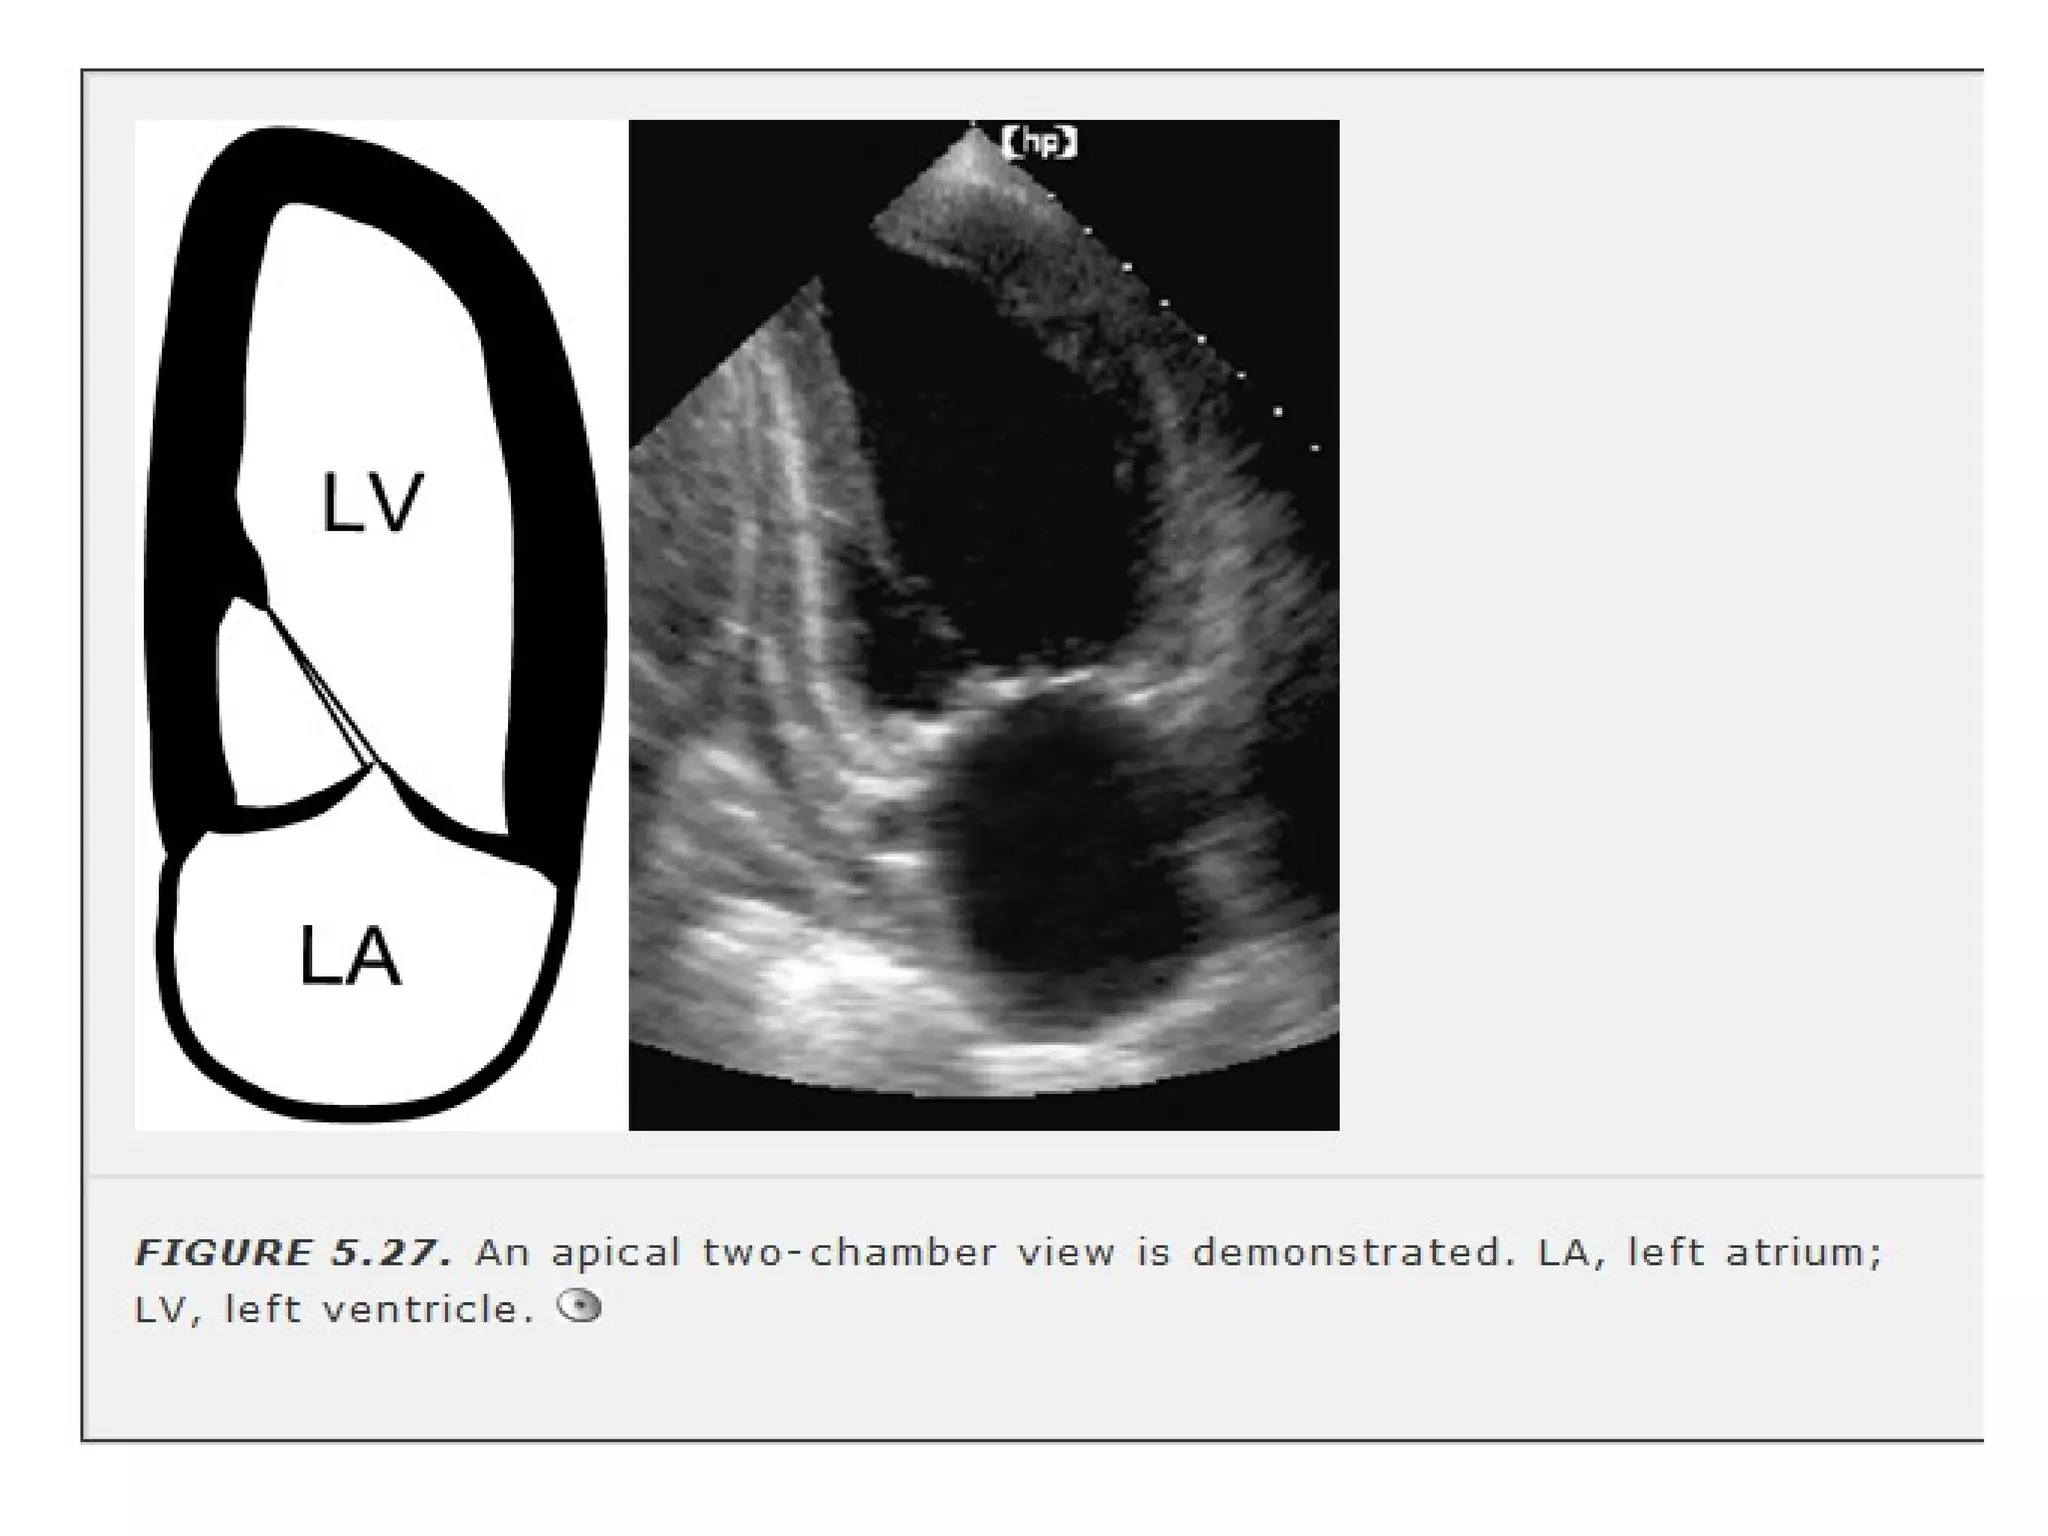

• Apical 2 chamber- rotating the transducer

CCW approx 60 deg.

Similar orientation to RAO

angiographic view LA

APPENDAGE IS VIEWED.